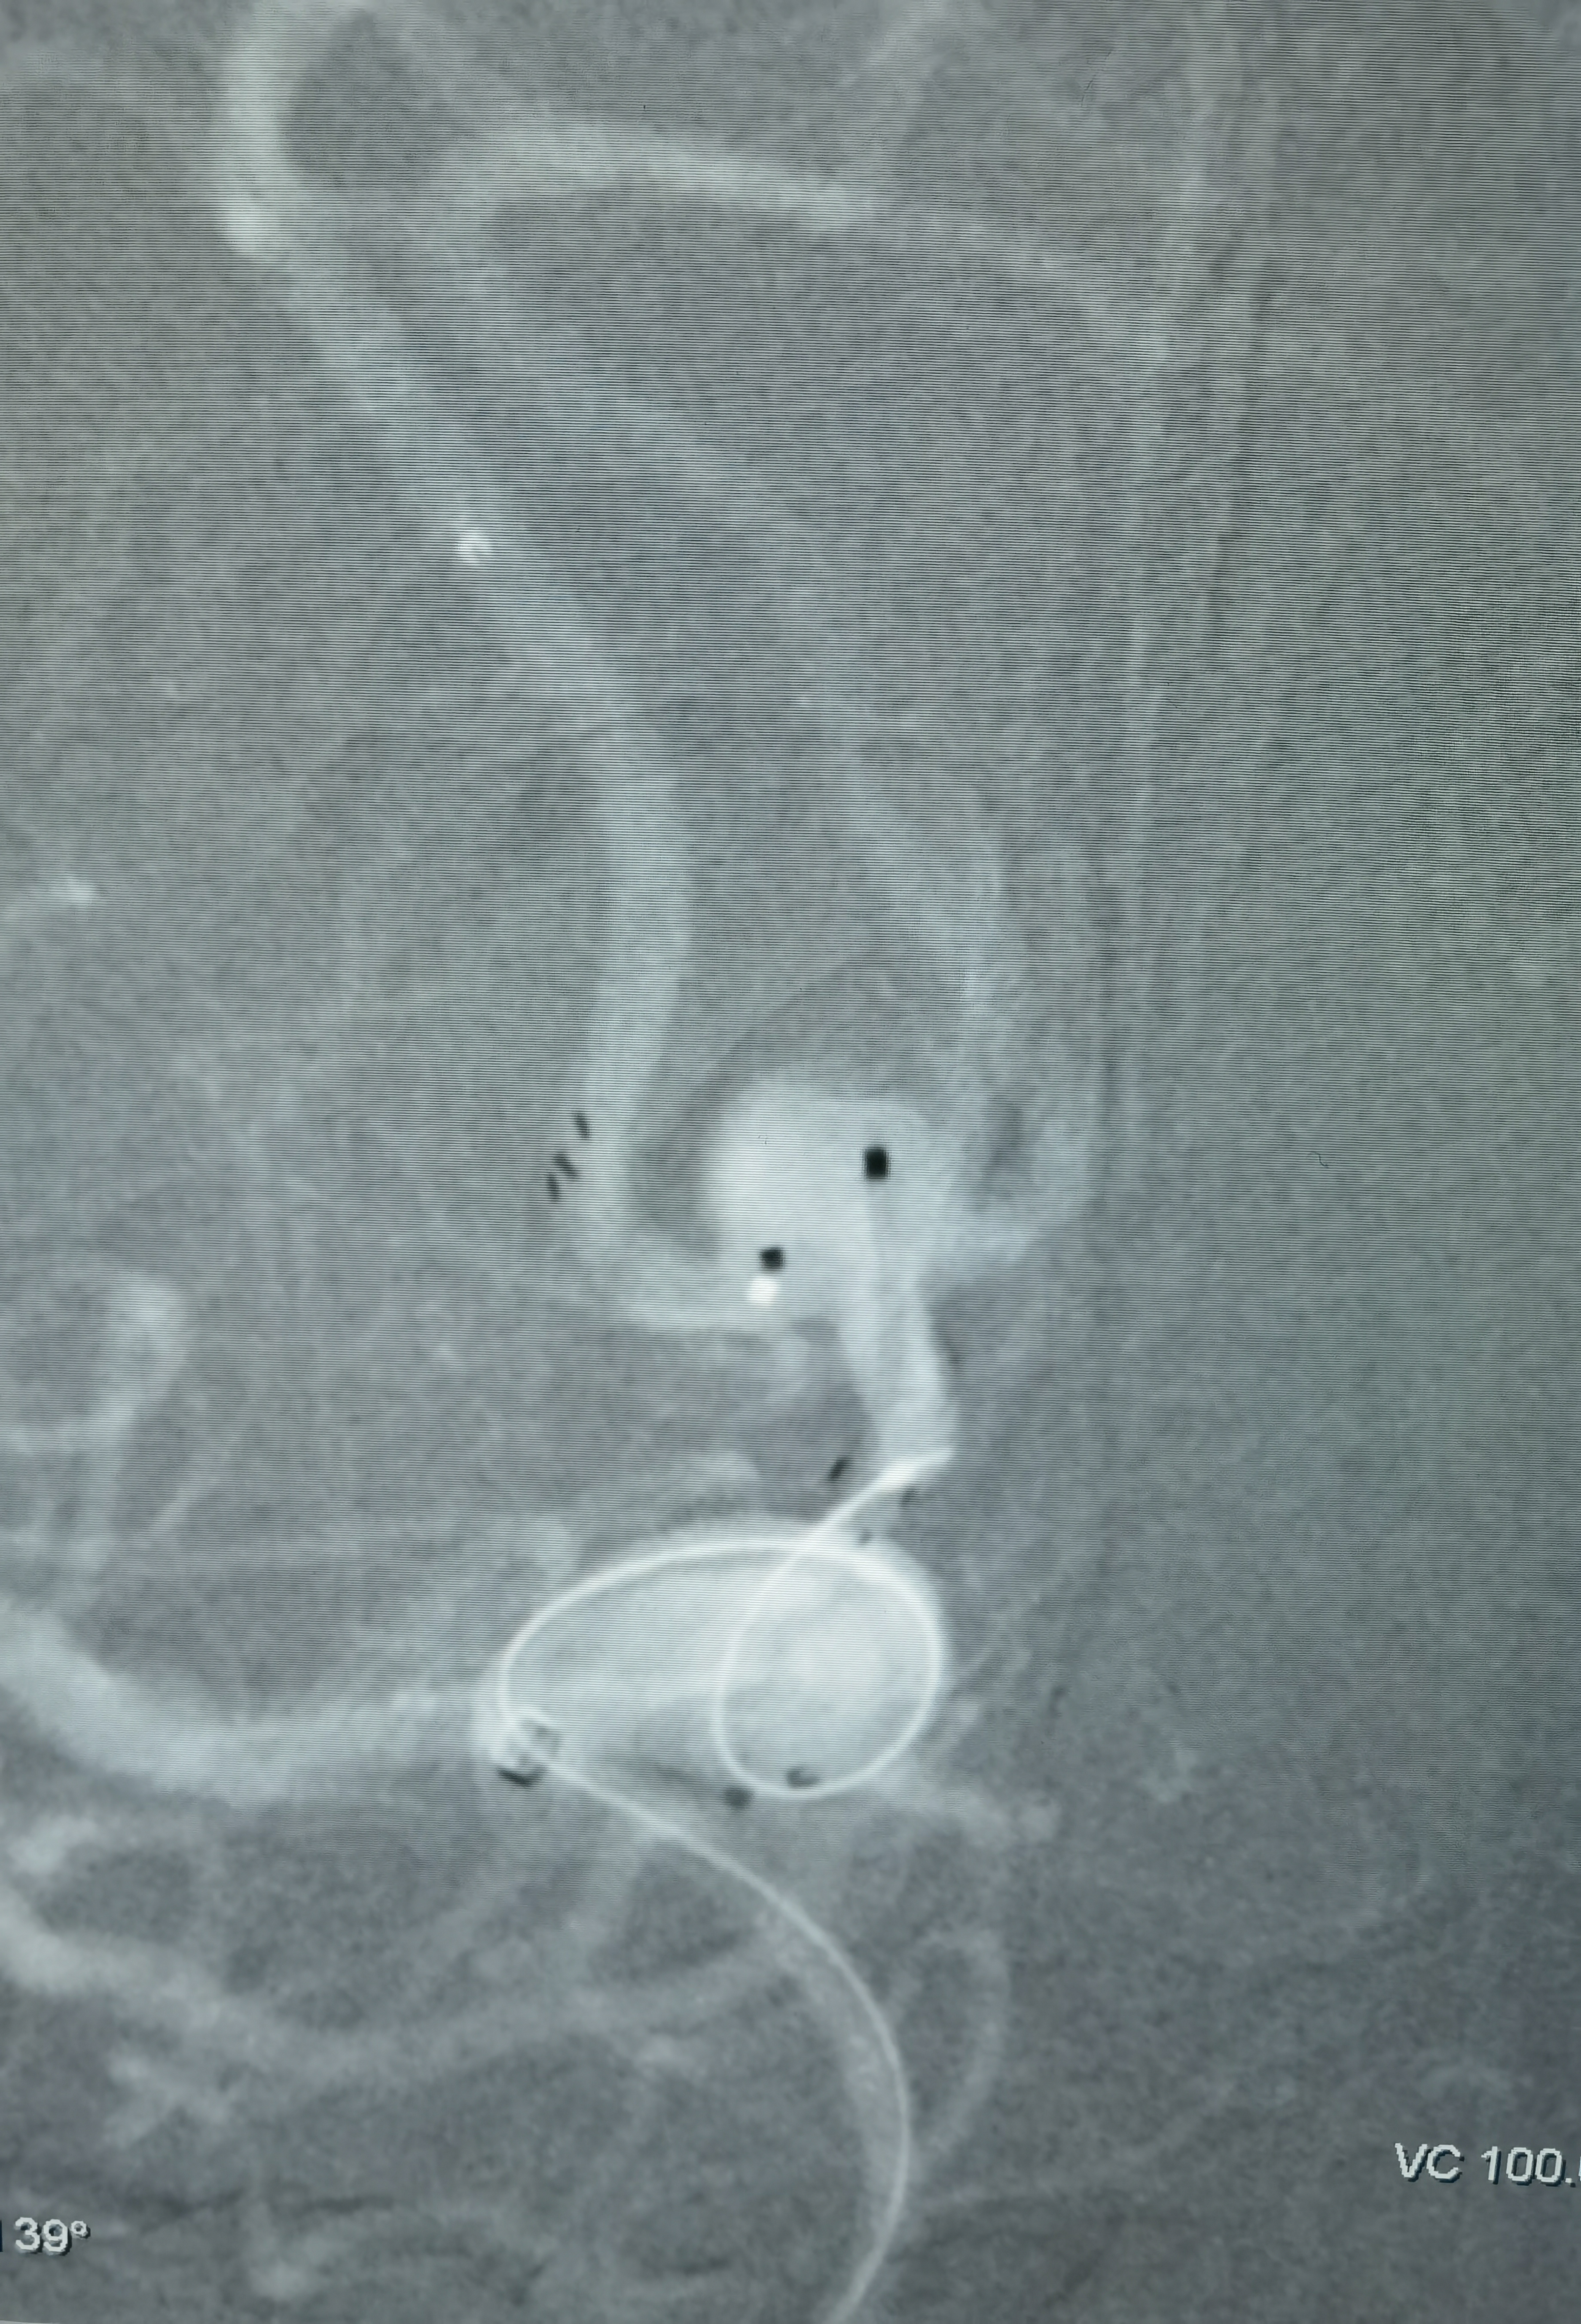

女性,63岁,体检发现动脉瘤,造影显示动脉瘤带子囊,破裂风险大,手术干预!

工作位造影